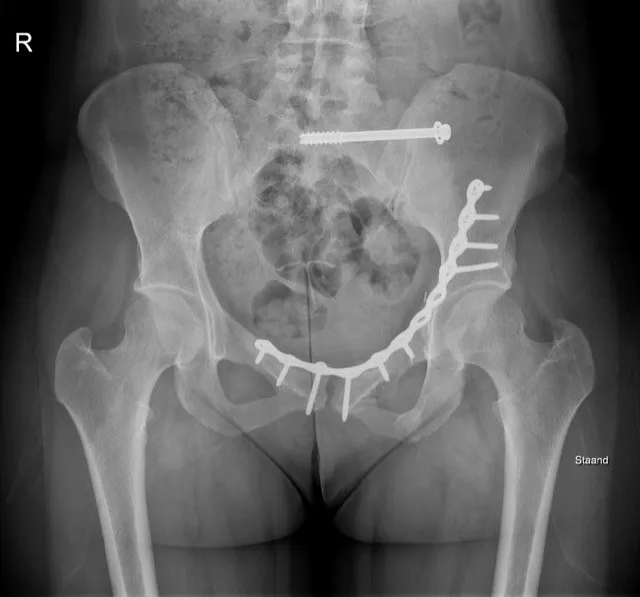

Stap 3: Operatie (bij instabiele of complexe breuken):Instabiele bekkenfracturen (waarbij de bekkenring zowel voor als achter gebroken is) en heupkomfracturen vereisen meestal een operatie. De traumachirurg bepaalt aan de hand van de breuksoort welke ingreep nodig is. Vaak wordt een bekkenbreuk na enkele dagen geopereerd, wanneer de conditie stabiel is en de weke delen minder gezwollen zijn. Tijdens de operatie worden de botstukken weer in de juiste positie gebracht en met platen en schroeven vastgezet (interne fixatie). Bij een bekkenringbreuk plaatst de chirurg meestal één of twee platen aan de voorzijde (ter hoogte van het schaambeen) en schroeven of platen achterin bij het heiligbeen om de ring te sluiten. Bij een heupkomfractuur (acetabulumfractuur) maakt men een opening langs de zijkant, voorkant en/of achterkant van de heup om de gebroken heupkom delen te herstellen en met schroeven/platen te fixeren. Soms wordt in eerste instantie een externe fixateur (tijdelijk) geplaatst en later de definitieve interne fixatie uitgevoerd (bijvoorbeeld als de patiënt eerst moet worden gestabiliseerd of als de huid zwaar gekneusd was). Na een operatie blijft de patiënt enkele dagen tot weken in het ziekenhuis. Er wordt vroeg gestart met lichte oefeningen voor benen en armen om de conditie te behouden. Afhankelijk van de instructies van de chirurg mag de patiënt beperkt gewicht zetten op de benen – bijvoorbeeld enkele weken niet of slechts 10-20 kg steun – om de genezing van de bekkenbreuk niet te verstoren. Revalidatie vindt plaats met kinesitherapie (fysiotherapie): oefenen van bedmobiliteit, vervolgens zitten, staan en geleidelijk leren lopen met hulpmiddelen.

Een bekkenbreuk is een ernstig letsel van de bekkenring, vaak veroorzaakt door een zwaar ongeval of bij ouderen door een val bij osteoporose. Typische symptomen zijn hevige pijn en onmogelijkheid om nog te lopen. De diagnose wordt gesteld met beeldvorming (RX en CT) en de behandeling varieert van pijnstilling en rust tot operatief vastzetten, afhankelijk van de stabiliteit van de bekkenfractuur. Vroege herkenning en aangepaste behandeling zijn cruciaal, want bij instabiele bekkenfracturen kan inwendig bloedverlies levensbedreigend zijn. Met de juiste aanpak – eventueel inclusief specialistische chirurgie – kan een bekkenbreuk goed herstellen. De revalidatie vergt geduld en inzet: men start voorzichtig met mobilisatie om complicaties te voorkomen. Uiteindelijk kunnen veel patiënten hun gewone dagelijkse activiteiten hervatten. Bij eenvoudige bekkenbreuken is volledig herstel haalbaar, terwijl complexere breuken soms restklachten geven.